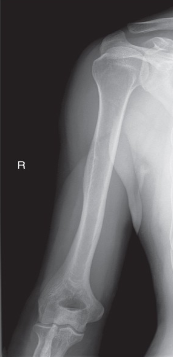

name the position/projection

AP humerus

evaluation criteria for AP humerus

entire humerus to include elbow/shoulder joints

greater tubercle in profile

medial/lateral epicondyles in profile